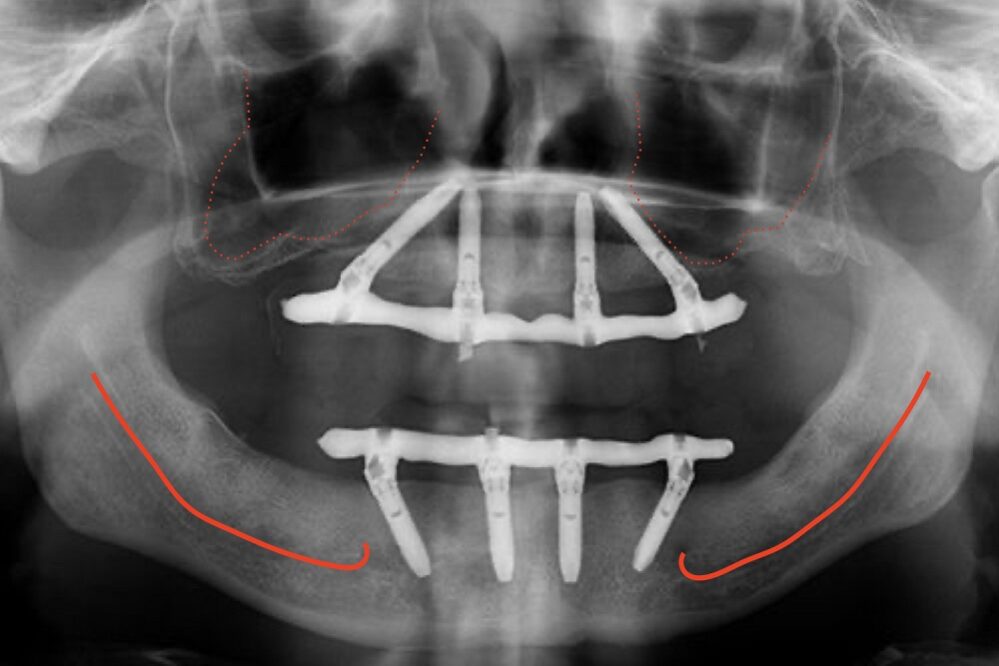

All-on-four therapy concept of the edentulous jaw consists of placing four dental implants and replacing twelve teeth in one jaw. Due to progressive bone loss in lateral regions of the lower and upper jaw or increase (pneumatisation) of maxillary sinus in the upper jaw and proximity of the mandibular nerve in the lower one, we often need big bone augmentations, so that we can ensure adequate bone volume for the integration of implants.

All-on-four therapy treatment enables rehabilitation of all lost teeth without the necessary bone augmentations. What is it about? There is often enough bone volume in the anterior part of the jaw to place the implants. By modifying the technique of an implant bed preparation, lateral implants are placed with inclination, so that the load field is increased, and consequently, we can replace a series of twelve teeth with the placement of only four dental implants.